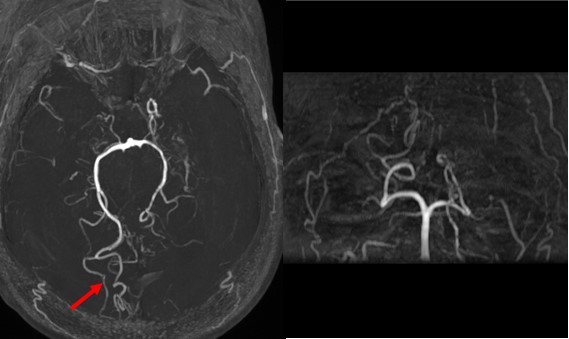

病例2 男,45y,胶质瘤术后3天

胶质瘤术后复查的检查,在临床中再常见不过,常规扫描方案头颅平扫+增强,目前只有部分医院会结合其他技术,例如灌注去综合评估患者术后情况。这次我们遇到了一例胶质瘤术后患者,申请单为头颅平扫+增强,图像如下:

T1上右侧额叶高信号,提示有出血,增强病灶强化,肿瘤未切除干净?

增强反映的是血脑屏障是否完整,患者做了手术,血脑屏障肯定是被破坏了,这时无法分辨是残余的肿瘤强化还是术后损伤。灌注可能给出答案,灌注反映的是组织的微血管分布和灌注情况,若有残余的肿瘤,则表现为灌注升高,正好我们在增强前做了不打药灌注3D ASL:

3D ASL显示病灶区低灌注,提示强化区为术后损伤,并不是残存的肿瘤。